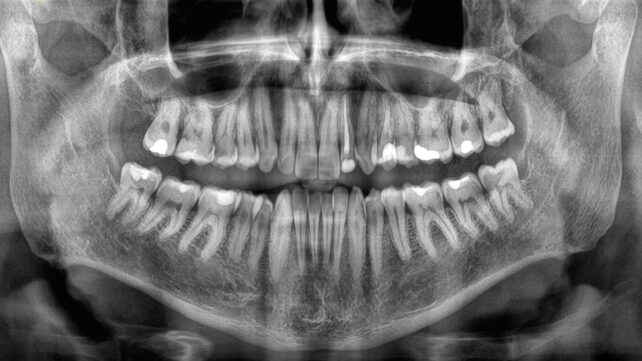

How fast we lose teeth in old age has been linked to a person's risk of dying in a comprehensive new study, emphasizing the importance of good oral health, and suggesting tooth loss could be a key indicator of other serious health problems.

Tooth loss has been connected to mortality before – generally, fewer teeth means a greater chance of an earlier death – but until now, there hasn't been any data on how losing teeth more quickly might affect this association.

To get that data, a team led by researchers from Sichuan University in China looked at tooth loss in 8,073 elderly people, tracking the rate at which they lost teeth against mortality, across an average of 3.5 years.